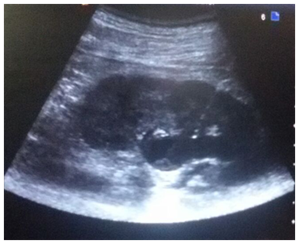

Patient was placed in the prone position, cleaning and draping of the region was done and skin infiltrated with 1% lignocaine. Following an incision with surgical blade (no 11) puncture needle (18/21 gauge) was introduced into the dilated pelvicalyceal system (PCS) under real time USG guidance using a trans abdominal convex probe of 4-9MHz Figure 1. Urine/pus was aspirated on PCS access for culture and sensitivity.

Figure 1 Longitudinal sonogram showing the entire course of the needle(arrow) traversing renal cortex with the tip in the dilated PCS

Precise point of entry was confirmed by a performing a nephrostogram and once the access into target calyx was confirmed the needle was exchanged over 0.035 Terumo guide wire. The tract was serially dilated, catheter introduced and guide removed after confirming correct placement of catheter tip. The nephrostomy tube was secured and urobag attached. Post procedure nephrostogram was performed Figure 2.